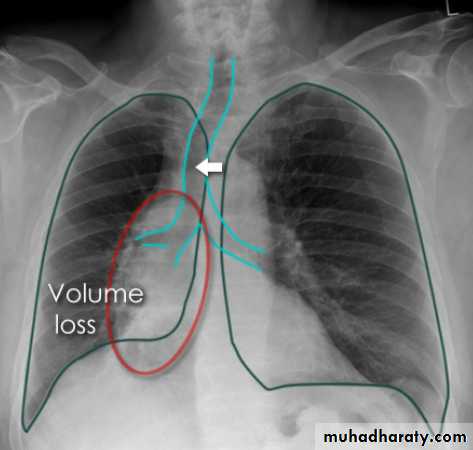

Lobar lung collapse

Lobar collapse refers to the collapse of an entire lobe of the lung. As such it is a subtype of atelectasis (although collapse is not entirely synonymous is atelectasis), which is a more generic term for 'incomplete expansion'. Individual lobes of the lung may collapse due to obstruction of the supplying bronchus.

Some features, however, are generic markers of volume loss and are helpful in directing ones attention to the collapse, as well as enabling distinction from opacification of the lobe without collapse (e.g. lobar pneumonia). These features include 5:

elevation of the ipsilateral hemidiaphragm

crowding of the ipsilateral ribs

shift of the mediastinum towards the side of atelectasis

crowding of pulmonary vessels or air bronchograms

Right upper lobe collapse has distinctive features, and is usually easily identified on frontal chest radiographs .

Radiographic features

Chest radiograph

Collapse of the right upper lobe is usually relatively easy to identify on frontal radiographs. Features consist of :

increased density in the upper medial aspect of the right hemithorax

elevation of the horizontal fissure

loss of the normal right medial cardiomediastinal contour

elevation of the right hilum

hyperinflation of the right middle and lower lobe result in increased translucency of the mid and lower parts of the right lung

right juxtaphrenic peak

A common cause of lobar collapse is a hilar mass. When a right hilar mass is combined with collapse of the right upper lobe, the result is an S shape to elevated horizontal fissure. This is known as Golden S sign .